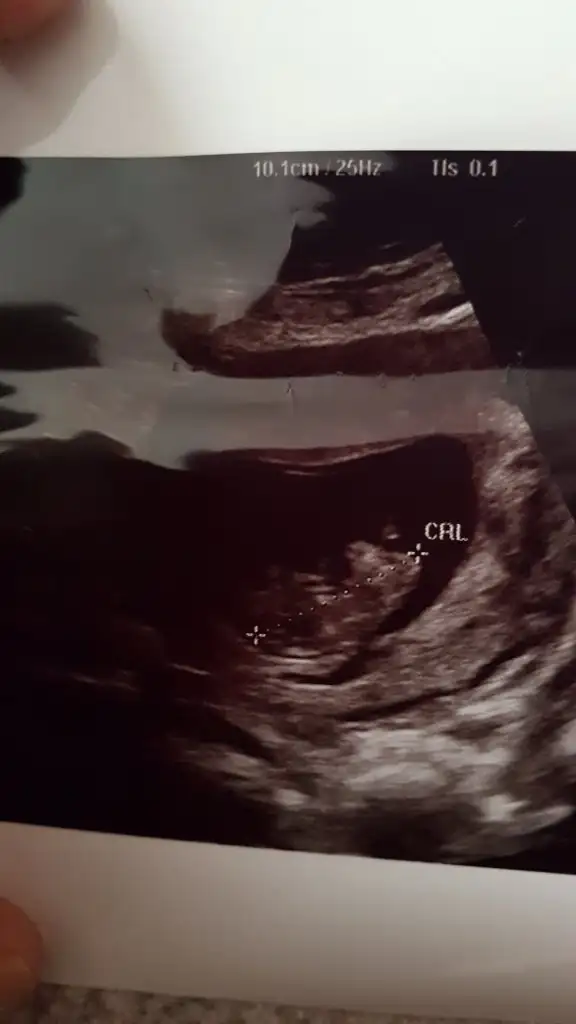

Nub için 11 yada 12 hafta kese için 6 yada 7 hafta usgnub icin erken ama kese pozisyon vs gore tahmini olan var mi? 9+4

Sen ne tahmin ettin arkadaşa ben erkek nubu gördüm umarım pozisyon değiştirmez bi arkadaşın hatta 2 arkadaşın dr ısrarla birine kız birine erkek demiş her ikiside 15 ve 16 haftasında benim tahminlerim tutu8 899eylulgelini burayada atarsan tahmin alırsın

Ben de çok net erkek dedim kafa duruş ama belli olmaz tabii senin ne dediğini de sordum hattaSen ne tahmin ettin arkadaşa ben erkek nubu gördüm umarım pozisyon değiştirmez bi arkadaşın hatta 2 arkadaşın dr ısrarla birine kız birine erkek demiş her ikiside 15 ve 16 haftasında benim tahminlerim tuturabbim gönüllerdekini saglıkla nasip etsin inşallah

Amin ınsallah tahminleriniz tutarr M mely15 sagol canm tahminin icinde rabbim hayrilisini nasip etsin ınsallhSen ne tahmin ettin arkadaşa ben erkek nubu gördüm umarım pozisyon değiştirmez bi arkadaşın hatta 2 arkadaşın dr ısrarla birine kız birine erkek demiş her ikiside 15 ve 16 haftasında benim tahminlerim tuturabbim gönüllerdekini saglıkla nasip etsin inşallah